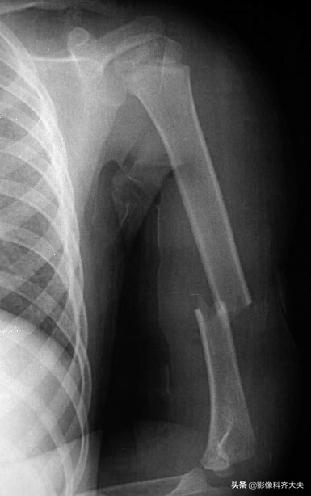

肱骨骨折

肱骨远端骨折后大量骨痂形成,骨小梁穿越骨折处